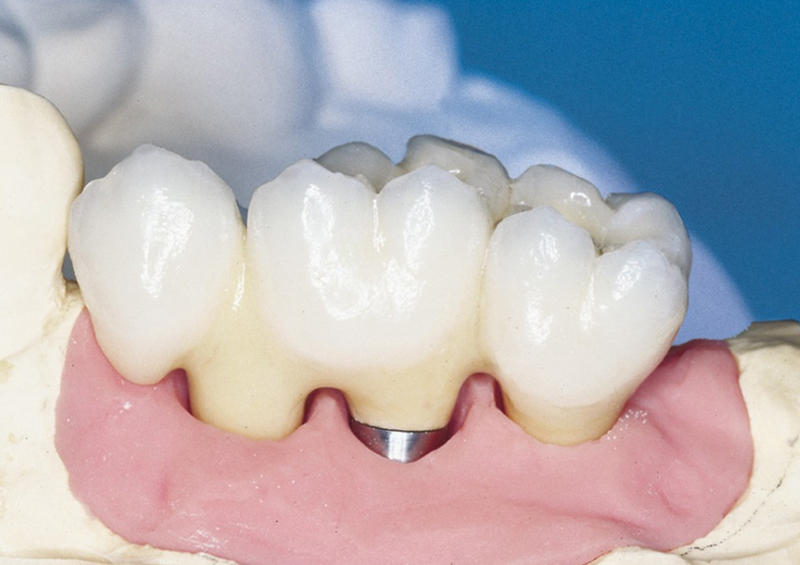

Náhrada jednoho zubu pomocí implantátu je možná také v postranním úseku chrupu. Při ztrátě většího počtu zubů ve frontálním nebo postranním úseku může být mezer uzavřena větším počtem jednotlivých implantátů.

Při ošetření pomocí jednotlivých implantátů zůstávají sousední zuby neporušené – intaktní. Při klasickém ošetření pomocí můstků musejí být tyto zuby obroušeny!

Protetické řešení může být pomocí můstku, který je kotvený na implantátech nebo pomocí jednotlivých korunek na implantátech.

- korunkami. Korunky nebo můstky mohou být na implantáty nacementovány nebo přišroubovány.